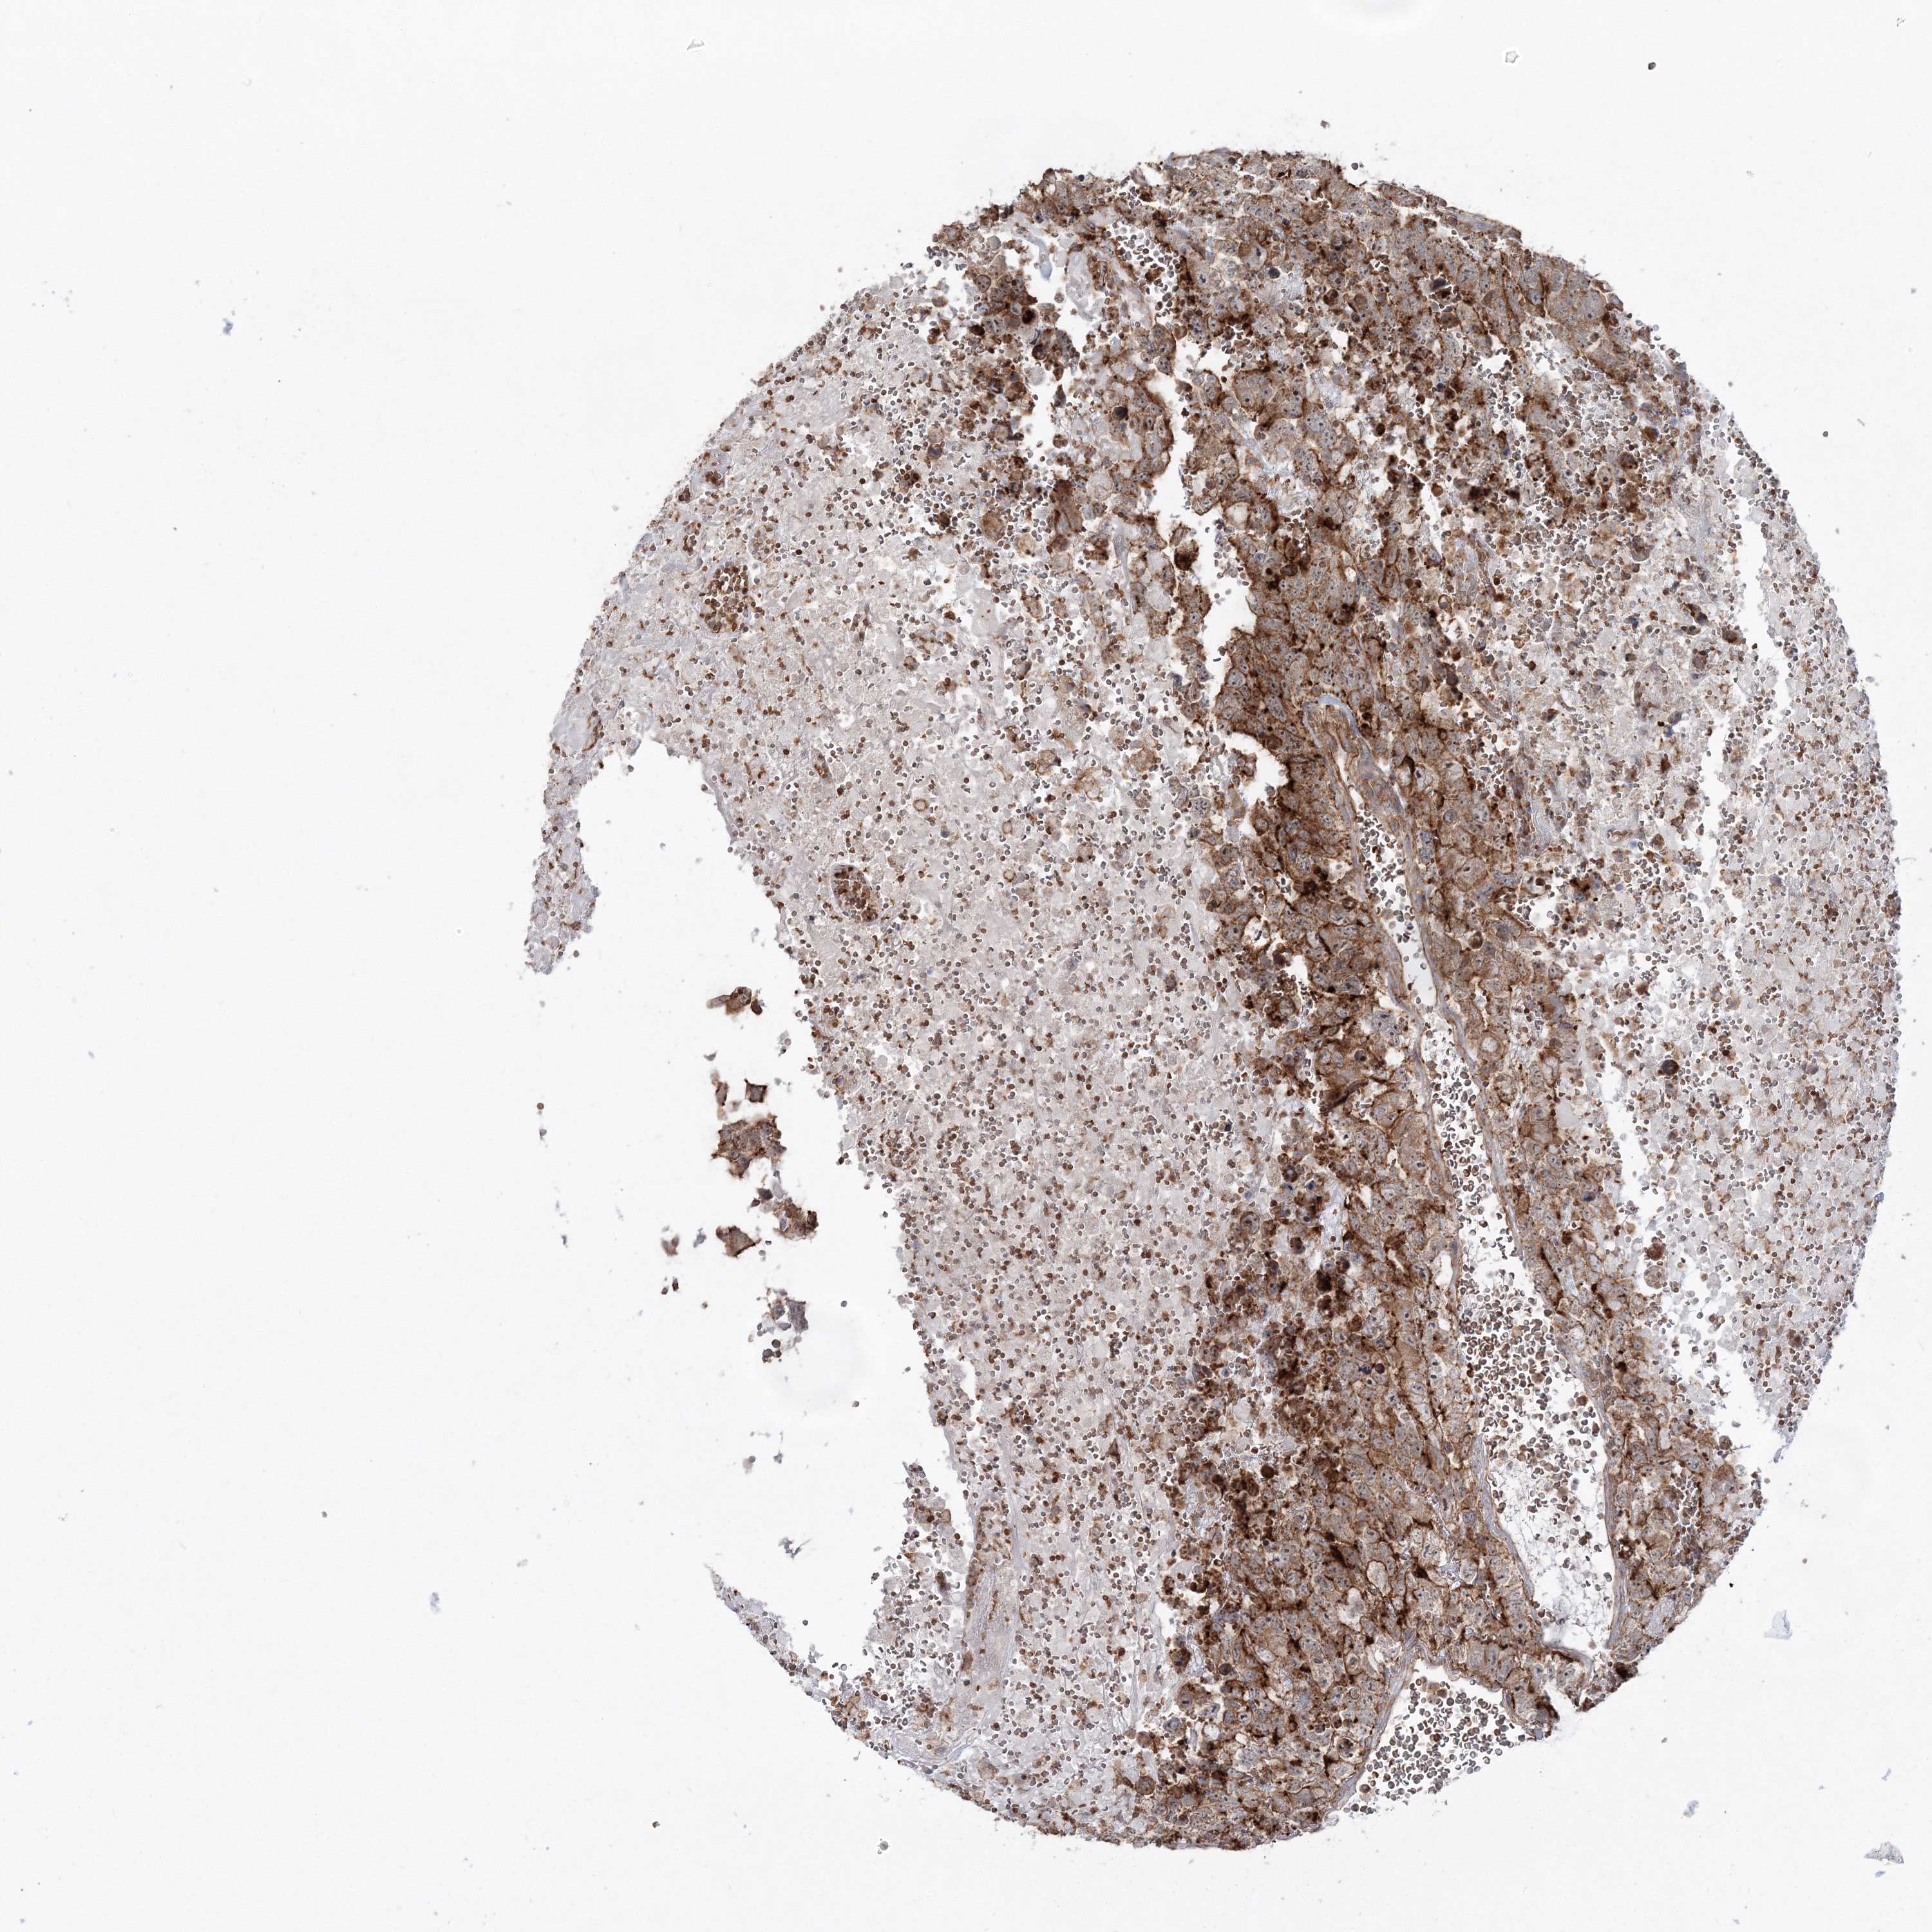

TESTIS CANCER - Protein expressioni

A mouse-over function shows sample information and annotation data. Click on an image to view it in a full screen mode. Samples can be filtered based on level of antibody staining by selecting one or several of the following categories: high, medium, low and not detected. The assay and annotation is described here.

Note that samples used for immunohistochemistry by the Human Protein Atlas do not correspond to samples in the TCGA dataset.

Antibody stainingi

Antibody staining in the annotated cell types in the current human tissue is reported as not detected, low, medium, or high, based on conventional immunohistochemistry profiling in selected tissues. This score is based on the combination of the staining intensity and fraction of stained cells.

Each image is clickable and will lead to virtual microscopy that enables deeper exploration of all samples and also displays staining intensity scores, fraction scores and subcellular localization as well as patient and tissue information for each sample.

Antibody HPA036428

Staining

High

Medium

Low

Not detected

Intensity

Strong

Moderate

Weak

Negative

Quantity

>75%

75%-25%

<25%

None

Location

Nuclear

Cytoplasmic/membranous

Cytoplasmic/membranous,nuclear

Carcinoma, Embryonal, NOS

Seminoma, NOS